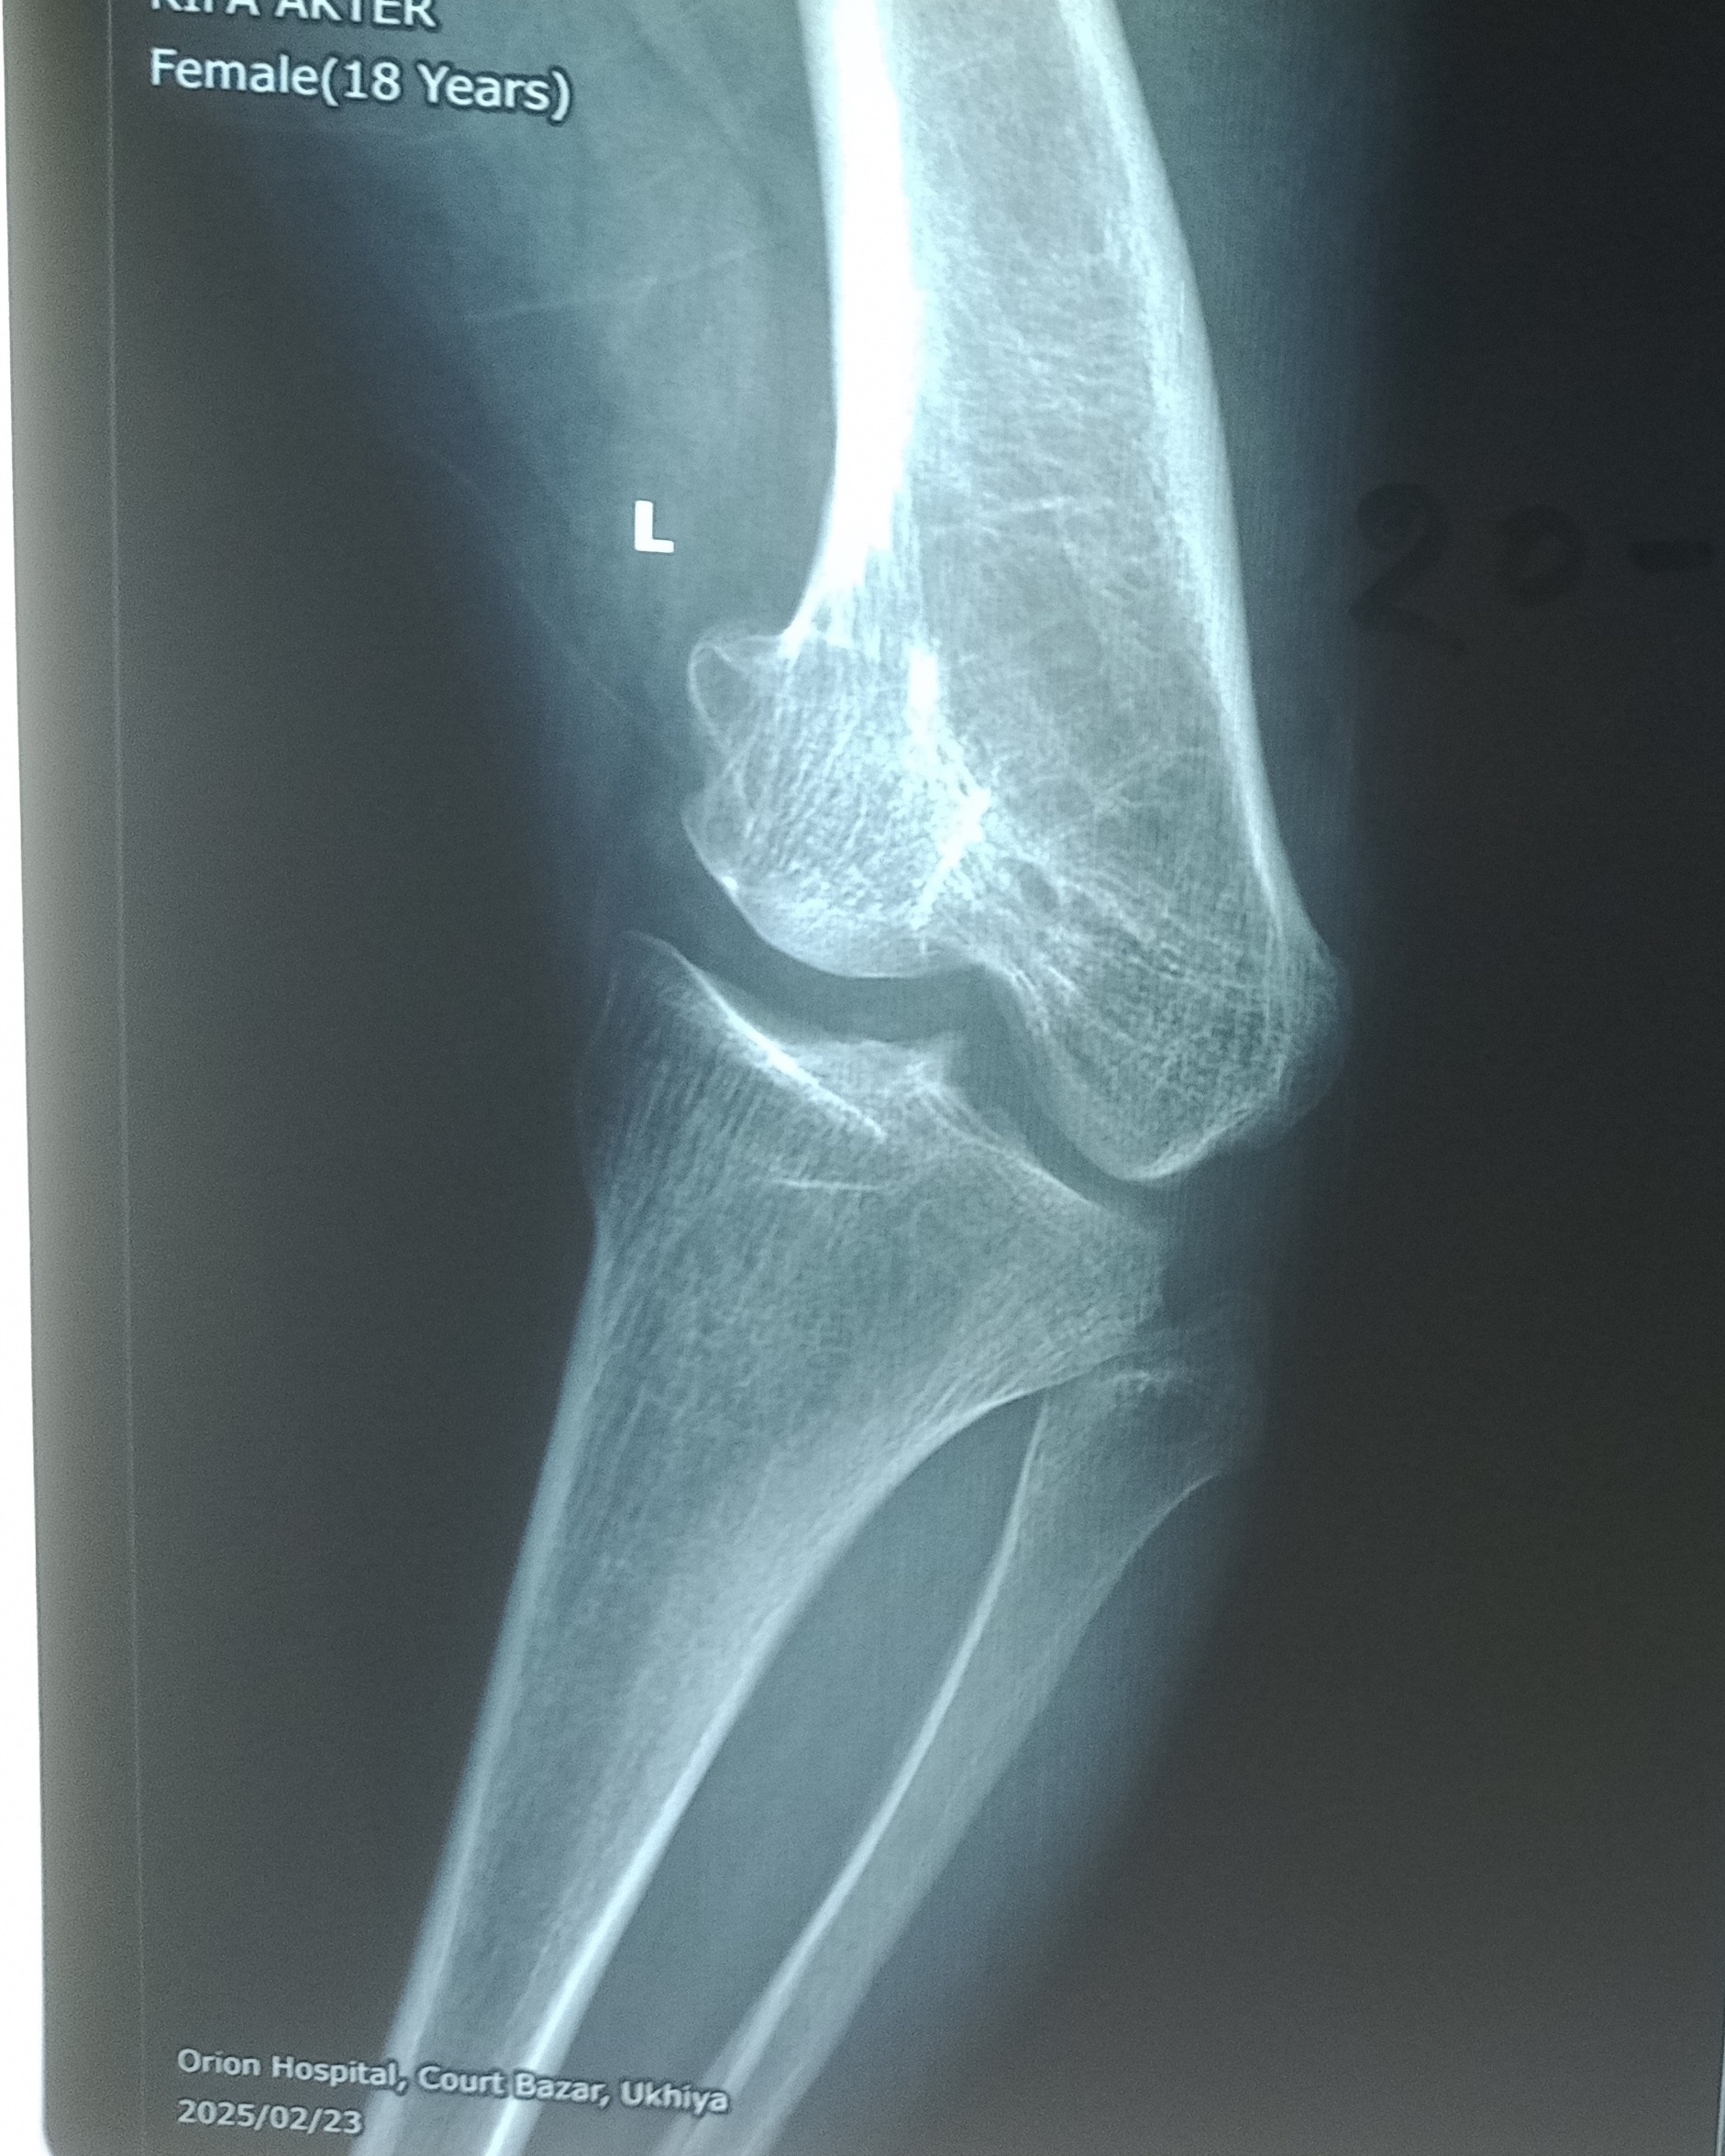

Rifa M… est née en 2001, elle habite un village proche d’Ukhia. Lorsqu'elle a commencé à marcher, sa maman a remarqué que ses jambes commençaient à se déformer. Comment faire soigner sa fille et où ? En 2007, lorsqu'un assistant médical SARPV s'est rendu à l'école de Rifa, la maman de Rifa a compris que leur fille pourrait être soignée au centre SARPV d’Ukhia. Ils ont consulté le kinésithérapeute de l’époque, qui a diagnostiqué un rachitisme et lui a prodigué un traitement. Après quelques années de traitement, sa déformation restait importante à gauche. En 2015, elle a été sélectionnée en vue d’une opération. C’est le Dr Gérard Py qui devait l’opérer. Hélas, durant les premières minutes de l’anesthésie, Rifa a fait un arrêt cardiaque. Grâce aux équipes médicales elle a pu être réanimée sans séquelles. Mais son intervention a été annulée. Ce fut une grande frayeur tant pour l’équipe que pour Rifa et sa famille. Il n’a donc pas été programmé de nouvelle intervention. Dix ans plus tard, ayant fini ses études secondaires, Rifa a décidé de revenir au centre en vue d’une opération. Elle n’avait plus peur et voulait en finir avec ses douleurs, la déformation de sa jambe gauche et… les critiques et moqueries des voisins. En 2025, elle a finalement été opérée avec succès par le Dr Py.